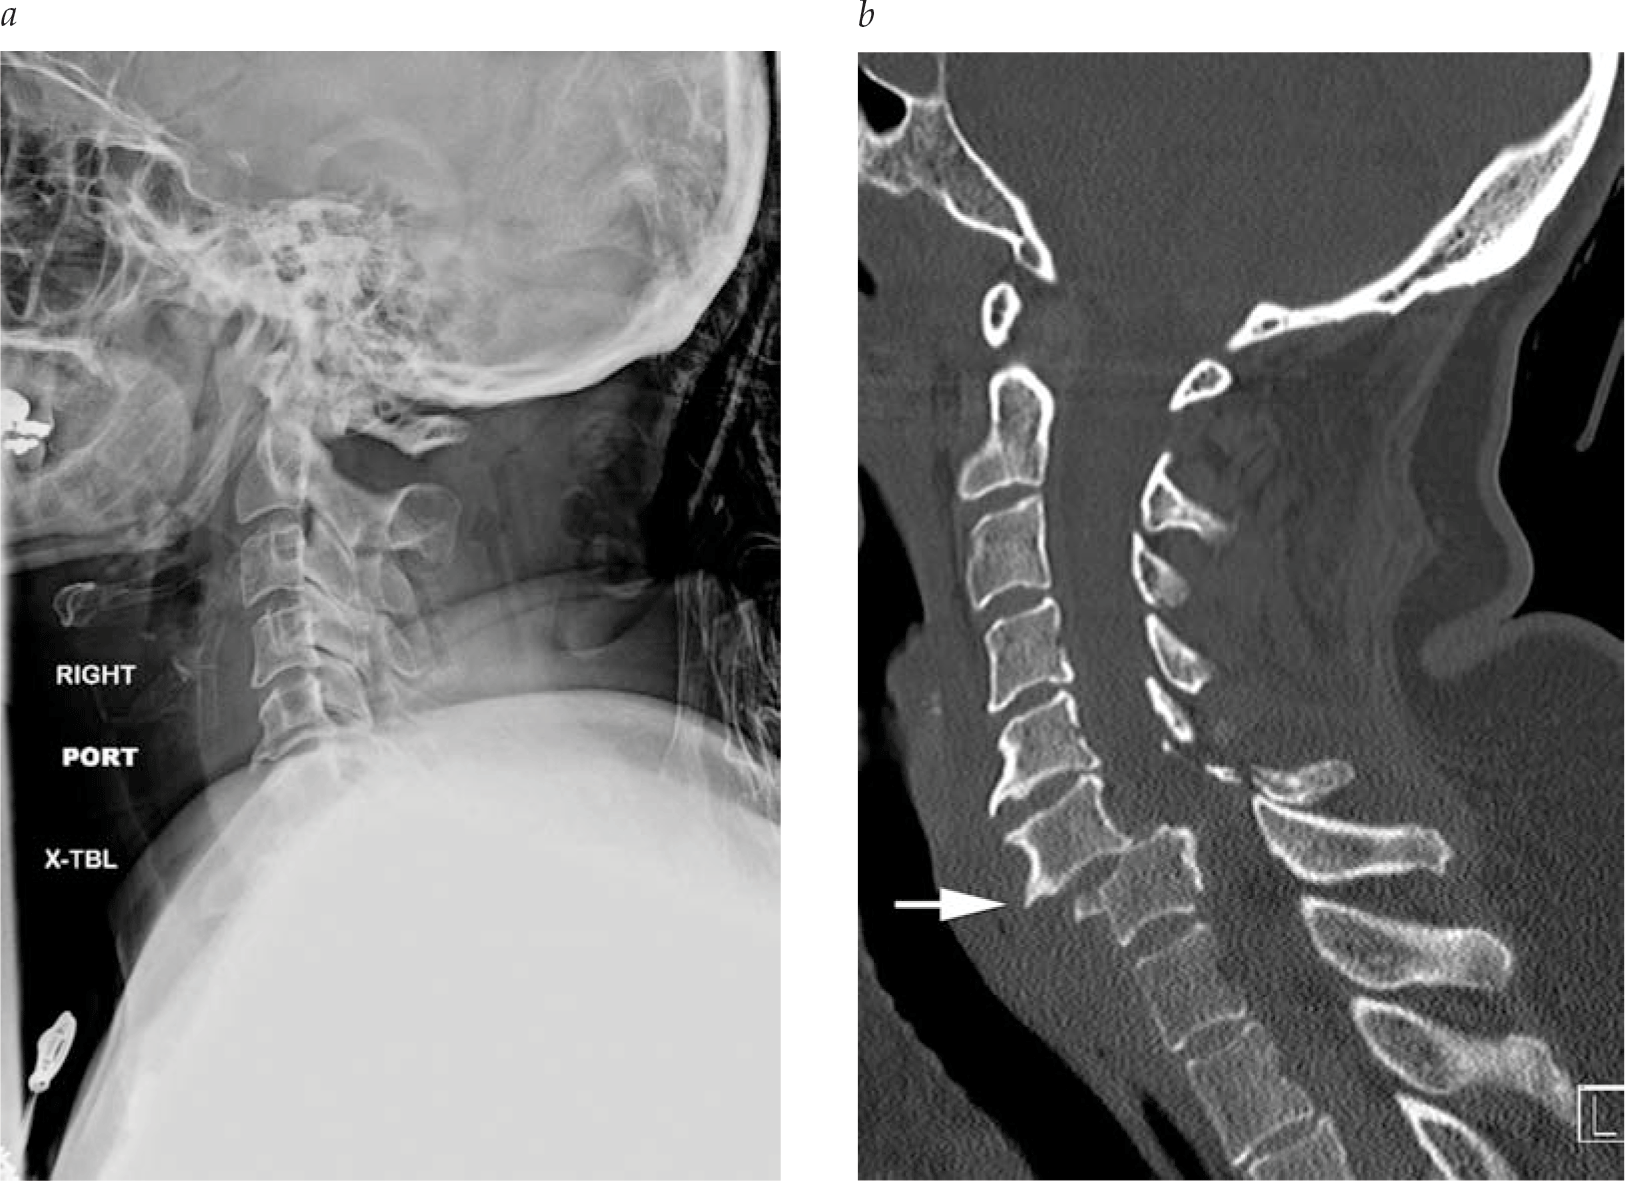

- Imaging studies have revolutionized the assessment of the trauma patient in the past three decades. Computed tomography (CT) provides excellent spatial and contrast resolution, especially when intravenous contrast is administered. Magnetic resonance imaging (MRI) provides soft tissue detail unavailable from other modalities.